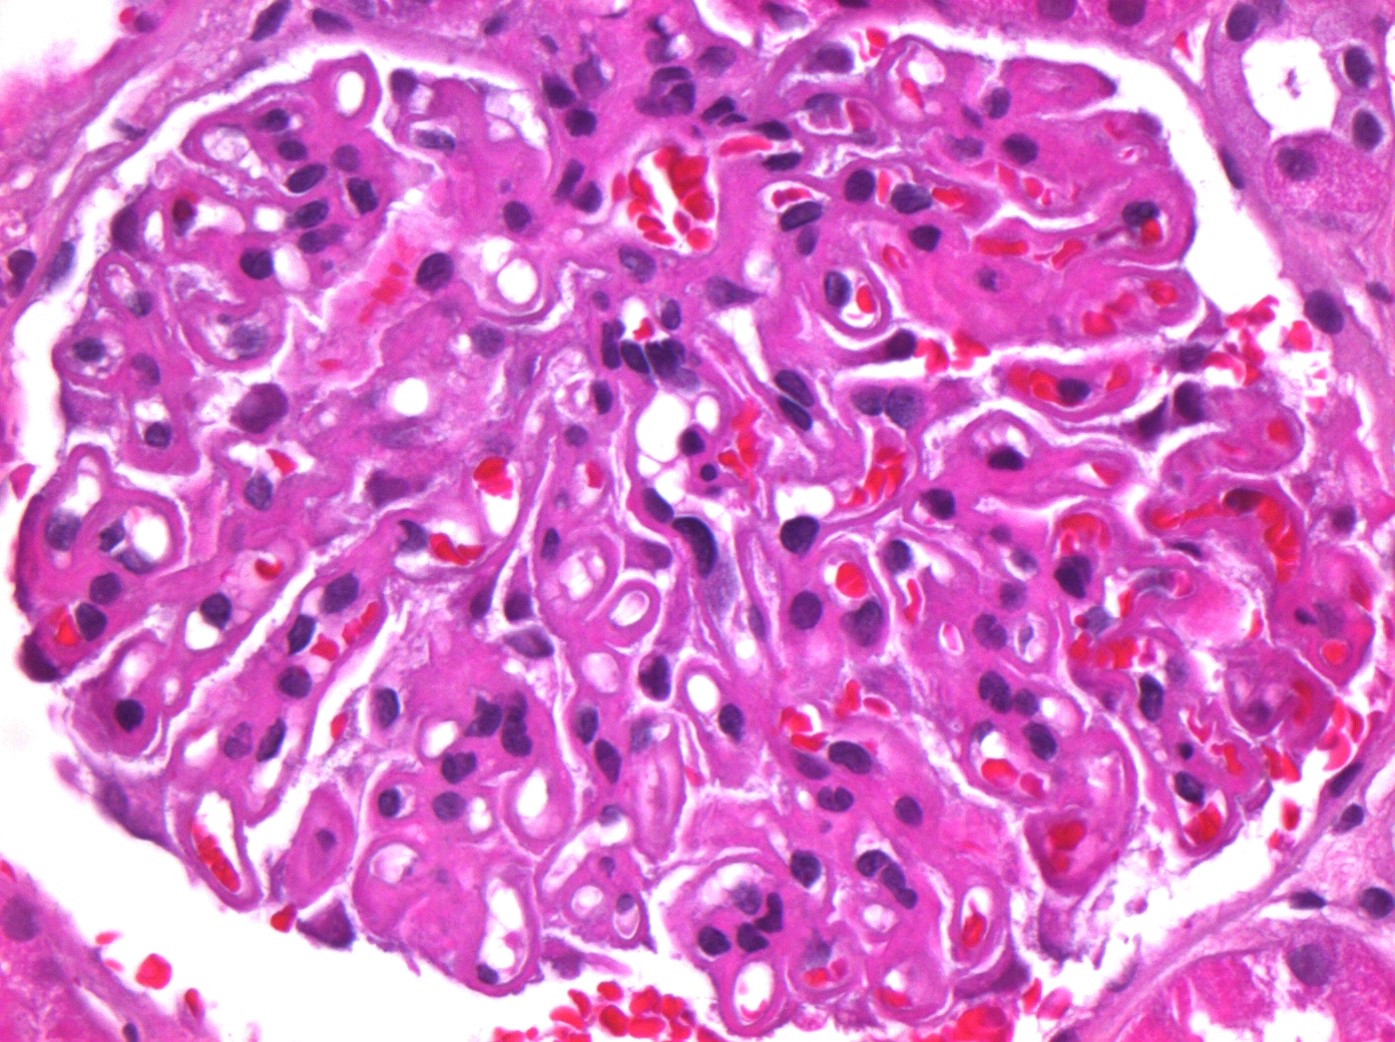

The typical histologic lesion on light microscopy is diffuse thickening of the glomerular basement membrane (GBM) throughout all glomeruli in the absence of significant hypercellularity. In some cases, "spikes" of GBM extending between the immune deposits may be seen with a silver stain.